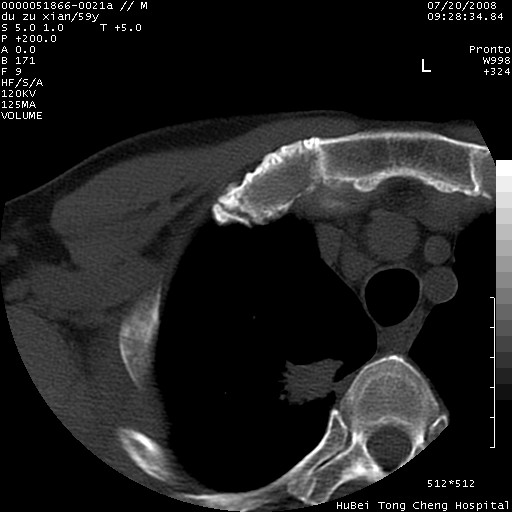

以下是引用宇宙ct在2008-8-25 23:21:00的发言:[br]右肺周围性肺癌并肋骨转移,纵隔淋巴结转移。

以下是引用zsl6918在2008-8-25 22:40:00的发言:[br]右肺周围性肺癌并肋骨转移,纵隔淋巴结转移。

以下是引用zy_zj在2008-8-26 15:24:00的发言:[br]单从病变本身,我倾向良性炎性病变,但肋骨转移了,所以说是考虑右肺周围性肺癌并肋骨、纵隔淋巴结转移可能性大。